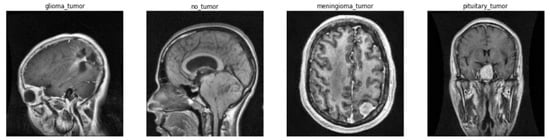

3.1. Image Pre-Processing